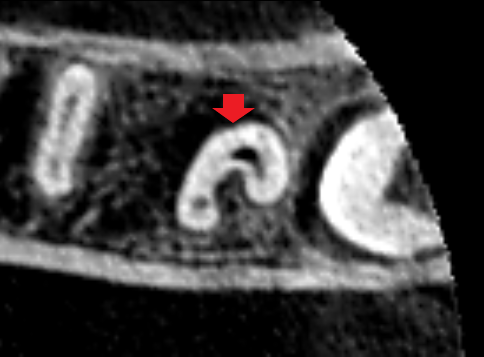

下顎第二大臼歯の初診時の冠状断のCT画像です。

赤い矢印の先に下顎骨を破りそうな位大きくなった膿の影がみられます。青い矢印の先は、下顎管という太い神経の通り道です。下顎管に達するくらいの大きな膿です。ここまで膿が大きいと一般的には、抜歯を勧められると思います。